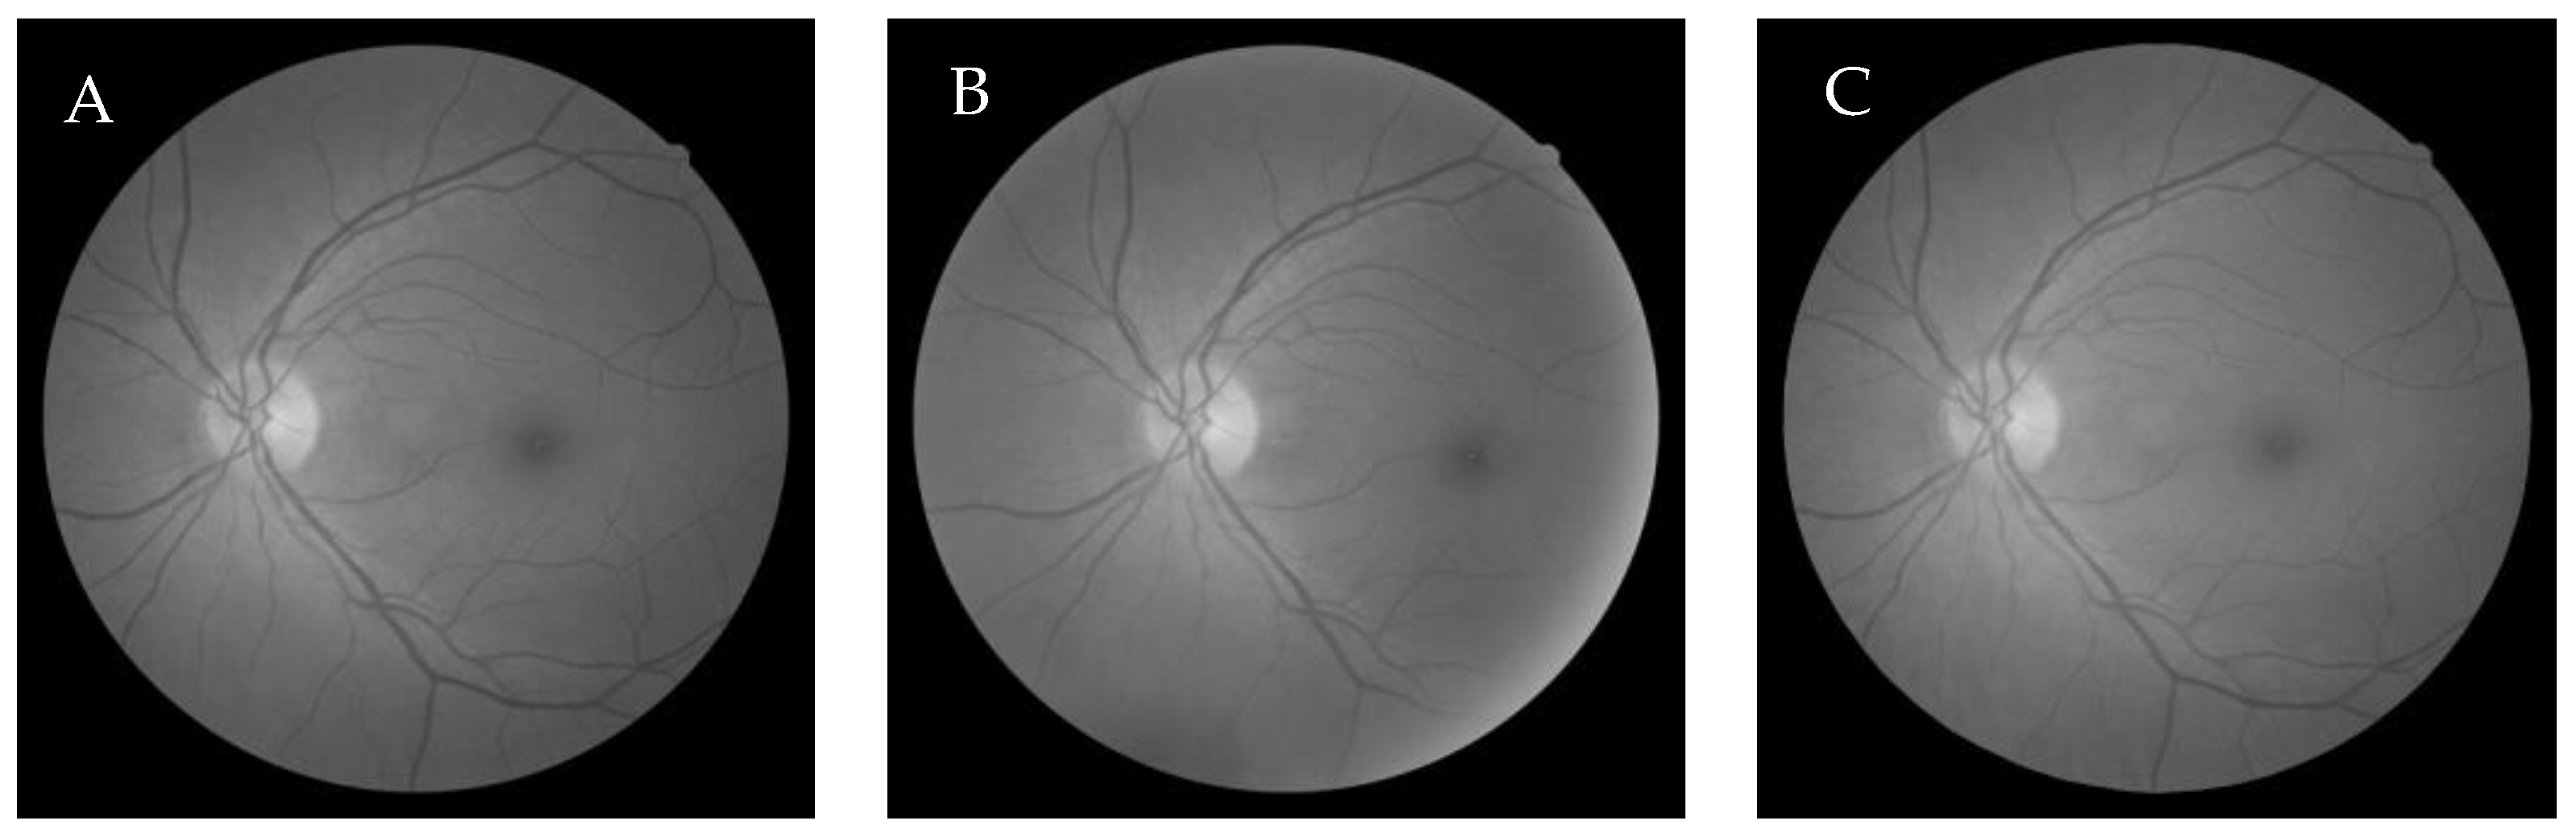

6.3. Comparative Study of the GWO-Based Different Demons Registration

| Optimized Values | Wang’s Demons | Tang’s Demons | Thirion’s Demons |

|---|---|---|---|

| MSE | 8.3585 × 10−5 | 2.7314 × 10−4 | 2.6885 × 10−4 |

| MJE | 5.3007 | 5.3464 | 5.3456 |

| NMI | 0.4920 | 0.4493 | 0.4500 |

| Correlation | 0.9977 | 0.9970 | 0.9970 |